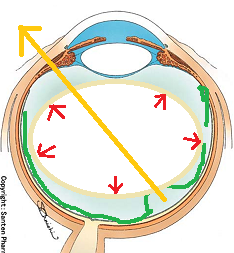

図の赤矢印の部分は視神経乳頭と言って、網膜が集まって束になる部分なのですが、実はこの部位のみ光を感じ取ることはできないのです。

自覚的には、マリオット盲点(視野が欠けて見えない部分)は、視界の中央から少し外側に存在します。(正確には、中心部から外側に15度位の部位)

マリオット盲点以外の部位が欠ける場合は病気となるのですが、視野が欠ける代表的な疾患として、緑内障があります(日本人の失明の原因の第一位)。